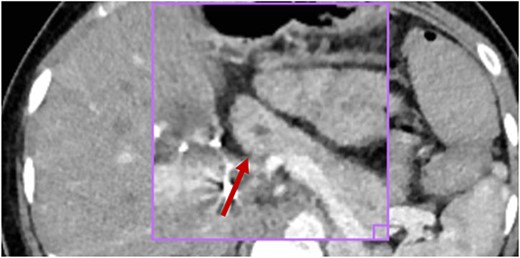

The patient has a history of four episodes of acute pancreatitis which also presented with abdominal pain, accompanied by elevated pancreatic enzymes (Table 1). During his first event, imaging studies were performed where the tomography showed a normal main pancreatic duct (Fig. 1) with no evidence of collections.

No inflammatory involvement of the body or pancreatic tail is observed; there is no alteration of the peripancreatic fat or collections at this level; visible wirsung canal measures 2.2 mm (red arrow).